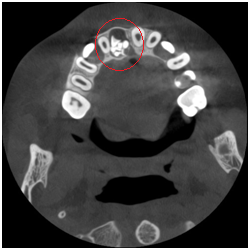

◆埋伏牙

◆牙瘤

◆由囊肿引起的骨质破坏